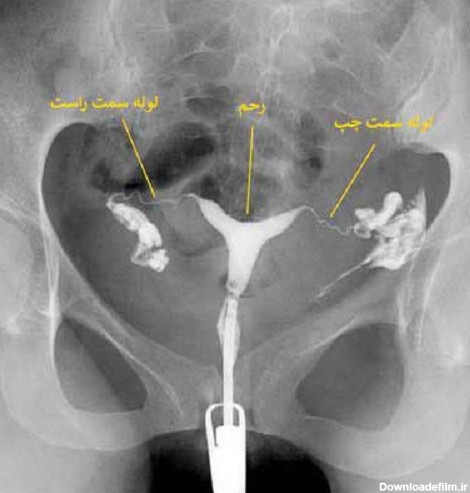

برای بررسی علت تأخیر باروری، باید سلامت اندامهای تولید مثل مورد ارزیابی قرار گیرند؛ یکی از روشهای تشخیصی که برای بررسی رحم و لولههای رحمی درخواست می شود، هیستروگرافی است. با این تست، پزشک از وضعیت داخلی رحم و لوله های رحمی مطلع میگردد و با توجه به نتایج حاصل از تست، در مورد نحوه درمان تصمیم خواهد گرفت. انجام این تست در ارزیابی ناباروری بسیار مهم است.